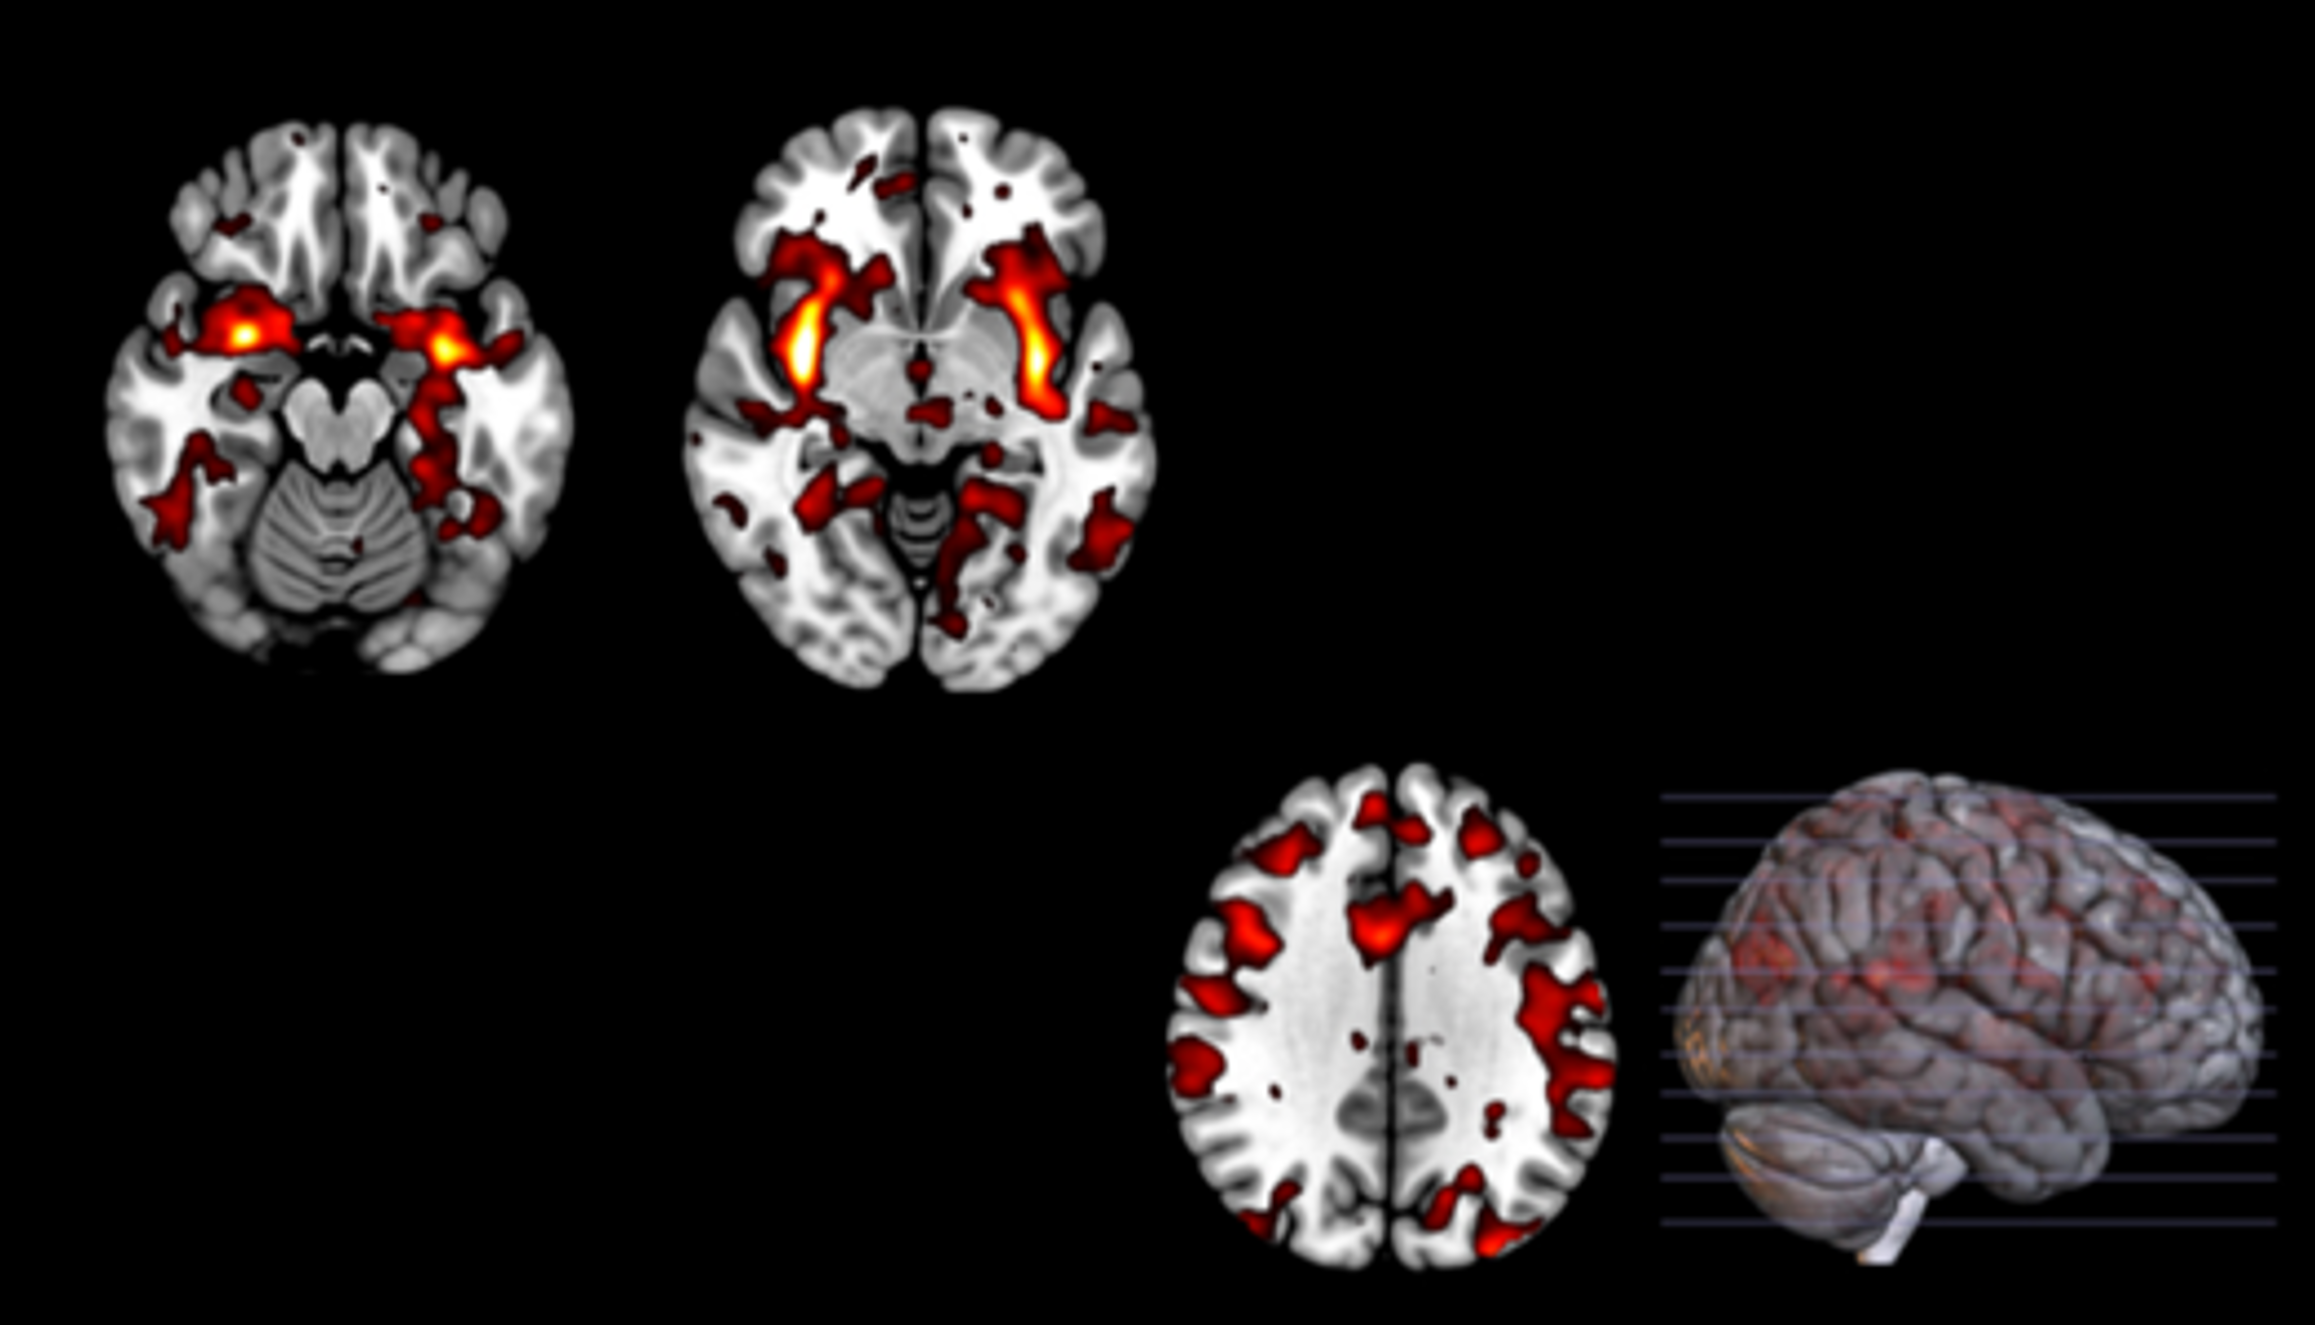

Multimodal Neuroimaging & Computational Neuroscience Research on Human Behaviors & Mental Disorders

Dr. Kang's Cerebral Computing Laboratory is dedicated to studying the brain mechanisms of cognitive/emotional processes and mental disorders. Using Multimodal-Neuroimaging, Psychophysiological, and Computational Methods, we investigate to understand how normal and abnormal brain processes generate complex behaviors. We also aims to develop cutting-edge methods to monitor and modulate neural activities to improve mental functions and psychiatric/neurological symptoms.